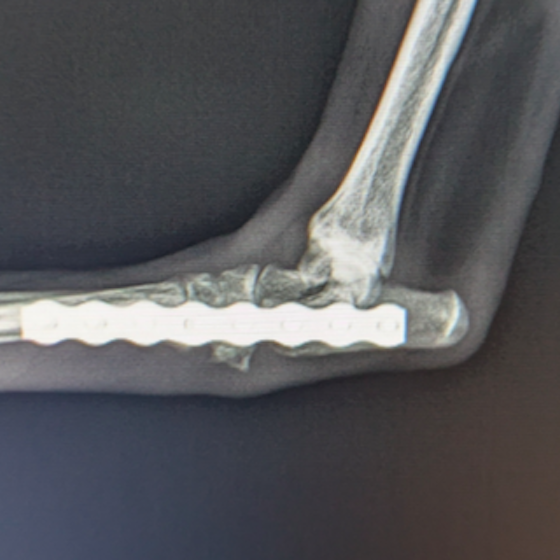

膀胱腫瘤(2025/11/25)

犬猫共に、膀胱内に腫瘤が発生することがあり、その場合には排尿しづらそうな様子や、血尿、頻尿といった、膀胱炎などと同様の症状がよく認められます。超音波検査を行うことで、膀胱内に腫瘤が形成されているかどうかを確認することが出来ます。また、カテーテルを用いて採材を行い、細胞診検査や遺伝子検査を行うことで診断を行います。診断後、腫瘤の発生状況などにより、外科的/内科的治療を検討していきます。膀胱内腫瘤を認めた場合には悪性腫瘍であることが比較的多いこともあり、普段と異なる排尿の様子が認められた場合などは、お早めにご相談下さい。